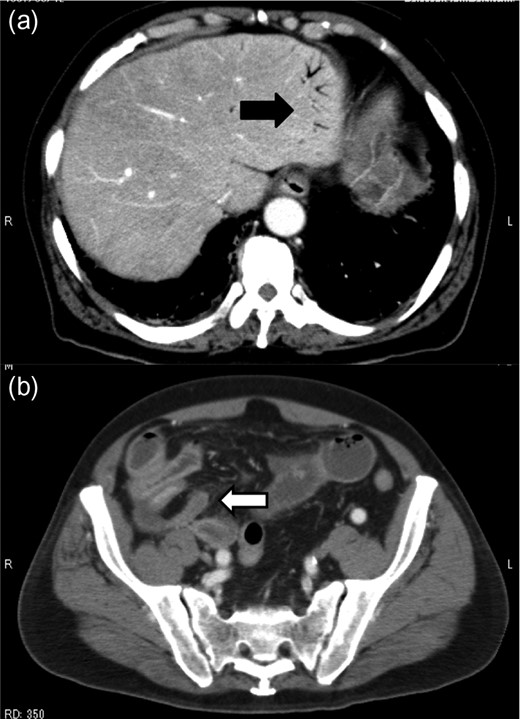

A 79-year-old man with acute abdominal pain had gone to a nearby hospital. As HPVG was detected by abdominal computed tomography (CT), he was transferred to our hospital for further examination and treatment. He had no remarkable past medical history. When he arrived at our hospital, his vital signs were relatively stable (body temperature: 37.2°C; blood pressure: 112/74 mmHg; pulse rate: 68 beats/min). However, physical examination revealed abdominal distention, rebound tenderness and abdominal guarding as signs of peritoneal irritation. The laboratory findings indicated acute inflammation (white blood cell count of 18 400/μL and Creactive protein concentration of 17.7 mg/dL), dehydration and metabolic acidosis (a level of base excess of −7.0 mmol/L). Creatine kinase was remarkably elevated (28 327 IU/L) (Table 1). Plain abdominal radiographs showed distention of the small intestine and suggested subileus (Fig. 1). Contrast-enhanced abdominal CT revealed HPVG (Fig. 2a), a contrast defect in a region of the small intestine, and a small amount of ascites around the intestine. There was no thrombus in any artery; however, the wall of the appendix was moderately thickened when we reevaluated the images retrospectively (Fig. 2b). We performed an urgent laparotomy with the diagnosis of generalized peritonitis caused by intestinal necrosis. A small amount of turbid ascites and a dilated small intestine were observed in the peritoneal cavity. Although the entirety of the small intestine and colon were explored, no intestinal ischemia was detected. Then, we found discoloration of the appendix with wall thickening. We thus made a clinical diagnosis of peritonitis caused by gangrenous appendicitis. Although the appendix wall was fragile, no macroscopic perforation of it was observed. We performed appendectomy and abdominal drainage. Based on the pathological findings, the patient was diagnosed with gangrenous appendicitis, with no evidence of malignancy (Fig. 3). Escherichia coli was positive in the ascitic culture. After the surgery, intravenous antibiotic treatment (meropenem) was administered. The patient subsequently went into septic shock with disseminated intravascular coagulation (DIC). He was therefore admitted to the intensive care unit (ICU), where he received blood purification therapy. The CT images on Day 7 after the surgery showed that HPVG had disappeared (Fig. 4). He left the ICU 7 days after the surgery and was discharged from the hospital another 10 days later.

Contrast-enhanced abdominal CT revealed HPVG (a, black arrow) and thickening of the appendix (b, white arrow).